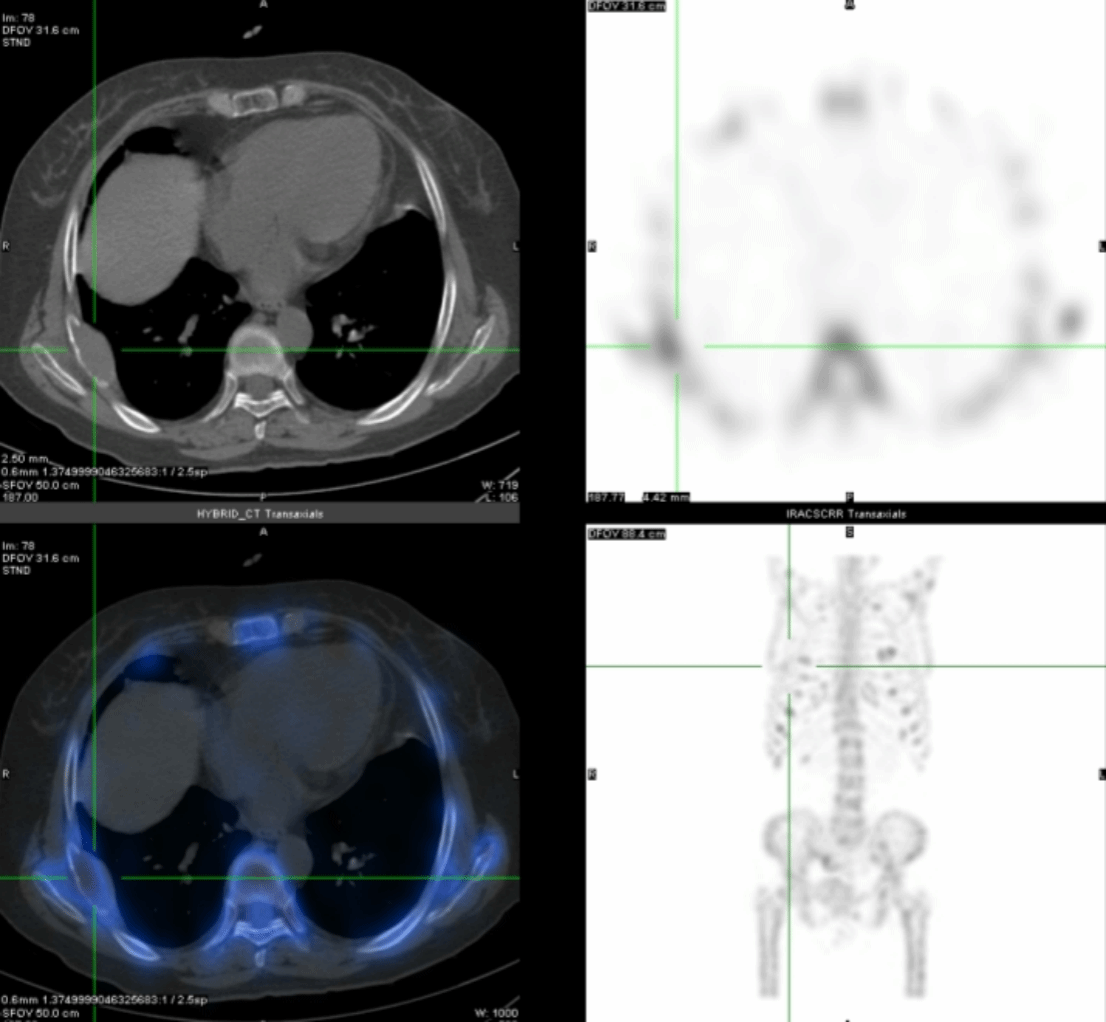

为了明确病变的位置,段阿姨又进行了核医学科的甲状旁腺显像(图5):

左侧甲状旁腺区显像剂浓聚较对侧稍增强,消退缓慢,提示可能为左侧甲状旁腺病变。

进一步的SPECT/CT断层融合显像(图6)显示,左上甲状旁腺形态增大,呈长条形,大小约1.3cm×0.6cm×4.5cm,并伴显像剂异常浓聚,考虑为功能亢进的甲状旁腺病变,首先考虑腺瘤。

后来段阿姨进行了手术治疗,病理为甲状旁腺腺瘤,术后段阿姨的血清钙恢复正常,PTH降低。